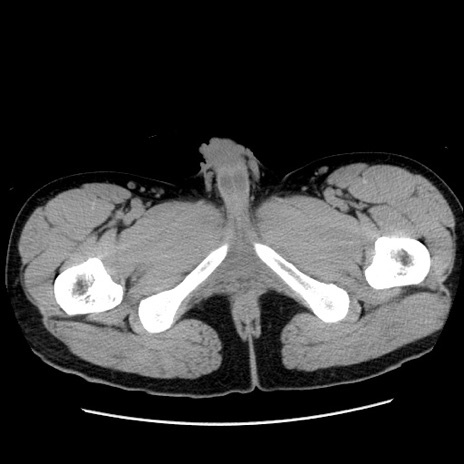

症例36(横断像)

【症例】20歳代 男性

【主訴】心窩部痛

【現病歴】今朝より上腹部痛あり。一旦軽快していたが再度出現したため救急要請。昨日夕に白身の魚を含む刺身を食べた。

【身体所見】BP 136/89mmHg、HR 74/min、BT 37.0℃、腹部:膨満、軟、心窩部に圧痛あり。反跳痛なし、筋性防御なし、腸雑音やや亢進あり。

【データ】WBC 17700、CRP 0.48